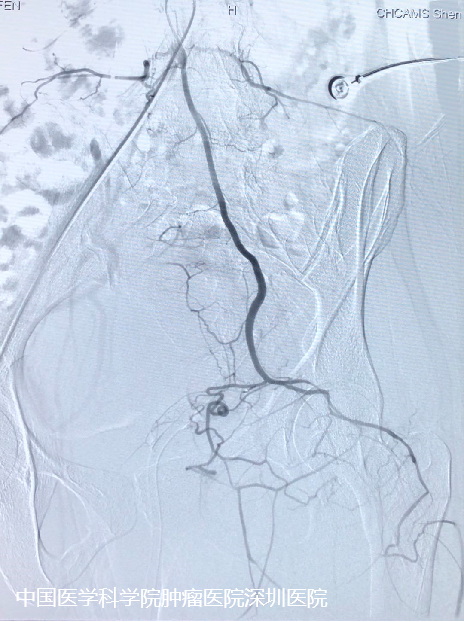

巧巧就诊时,肿瘤的压迫已经让她跛行、行动不便,排尿、排便困难,这个肿瘤已经到了必须治疗的地步。这种最大径接近30cm的巨大畸胎瘤可以说是很罕见的,手术风险极高,可能会出现肠道损伤、膀胱尿道损伤、生殖系统损伤、血管神经损伤、大出血、甚至失血性休克等。 骶尾部巨大肿瘤切除对外科医生来说一直是个极大的挑战。经科室讨论后向医务部报备重大手术申请,在王绿化院长、王东文副院长的主持下,总院骨科许宋锋教授立即会同泌尿外科王东文副院长及姜焕荣教授、妇科孙力教授、麻醉科李泉教授、介入治疗科宋鹏教授、胃肠外科李景文教授、骨科付来华教授等进行多学科讨论。 术前影像资料 制定了严密的手术计划——术前介入科行供瘤血管栓塞及腹主动脉球囊植入(以备术中临时阻断血供),麻醉选择控制性降血压以减少出血,妇科、泌尿外科及胃肠外科护航,在腹主动脉球囊阻断下行单纯后路骶尾部巨大肿瘤切除术。 本手术主要难点: 1.预防大出血——术前肿瘤血管栓塞、术中球囊阻断及控制性降血压。 2.术中注意保护结直肠、子宫、卵巢、输尿管、腰骶部神经和髂血管等。 3.肿瘤切除后盆底肌肉的修复和重建等。 术前栓塞 制定计划后,由骨科付来华教授主刀,许宋锋教授、介入治疗科宋鹏教授联合,2021年1月在全麻下进行了“骶尾部巨大软组织肿瘤切除 + 盆底软组织修复 + 血管神经探查松解”手术,手术时长近6小时,出血不足400ml。手术完美保护了盆腔重要脏器(直肠、子宫、尿道等),避免了术中大出血及骶尾部神经损伤。 “定时炸弹”顺利切除 肿瘤多学科诊疗很关键 巧巧的手术很成功,术后恢复也很好。现在巧巧终于摆脱了这个困扰了她25年的阴影,开开心心迎接她的新生活。第一次复查的她,已经穿上了漂亮的衣服,重拾自信。 主管医生介绍,畸胎瘤可能与胚胎期生殖细胞异常分化等因素有关,发病率为1/40000至1/20000,女性多发,发病率是男性的3-4倍。 畸胎瘤是先天性疾病,最常见的部位是卵巢,但发生于骶尾部是非常罕见的。此次手术难度巨大,最终通过多学科的努力,不仅完整的切除肿瘤,而且很好的保护了盆腔内的脏器。对于年轻的巧巧来说,本次手术也不会影响她的生育功能。 专家建议,在发现异常肿物或肿瘤时,避免盲目就医,有针对性的找到肿瘤专科医院就诊,避免延误就医导致病情恶化。 777全讯白菜网的多学科诊疗模式对于肿瘤的“精准治疗”和“个体化治疗”具有重大意义。